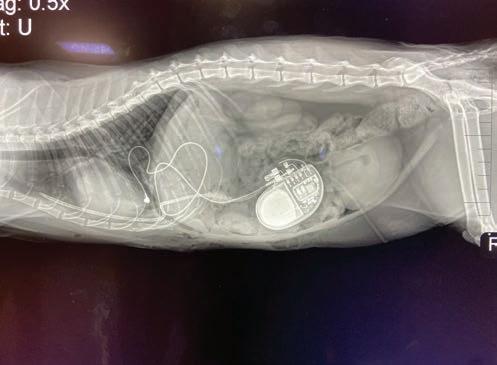

Cash (far left) was one of the first dogs in Charlotte to receive a pacemaker. A postoperative X-ray (left) shows a pacemaker generator in a cat’s abdomen and the lead connected to his heart.

The cost for pacemaker placement in dogs and cats usually runs between $3,500 and $5,000, and it can extend a pet’s life by three to ve years. For pets who weigh more than ve pounds, it’s a 45-minute, minimally invasive procedure followed by a night of observation at the animal hospital. (It’s more invasive for the tiny ones.)

The vet attaches a battery—a thin disc about two inches in diameter—to wires inserted into a neck vein that leads to the heart muscle. The generator monitors the heartbeat and emits impulses to restore the rate when it lags. It’s practically invisible, stitched beneath the skin and hidden under fur. As with all medical procedures, there’s risk. But typically, the biggest postsurgery hurdles are a six-week rest period, follow-up appointments, and switching from collars to harnesses.